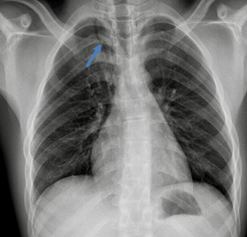

At age 16, a follow-up ultrasound identified asymmetry in the seminal vesicles, indicating congenital agenesis of the left seminal vesicle. Suspecting Zinner syndrome, an abdominal-pelvic magnetic resonance imaging (MRI) was performed, confirming left renal agenesis (Figure 1), ipsilateral agenesis of the seminal vesicle (Figure 2) along with a periurethral cyst (Figure 3) and a hypotrophic left testicle, thus confirming the diagnosis. The patient reported no abdominal, pelvic or testicular pain and no lower urinary tract symptoms. Clinical, imaging and laboratory follow-up were maintained, with the patient remaining asymptomatic throughout and retaining a glomerular filtration rate within the normal ranges.

Figure 1. Coronal T2-weighted MRI of the abdomen demonstrating agenesis of the left kidney, with compensatory hypertrophy of the right kidney.